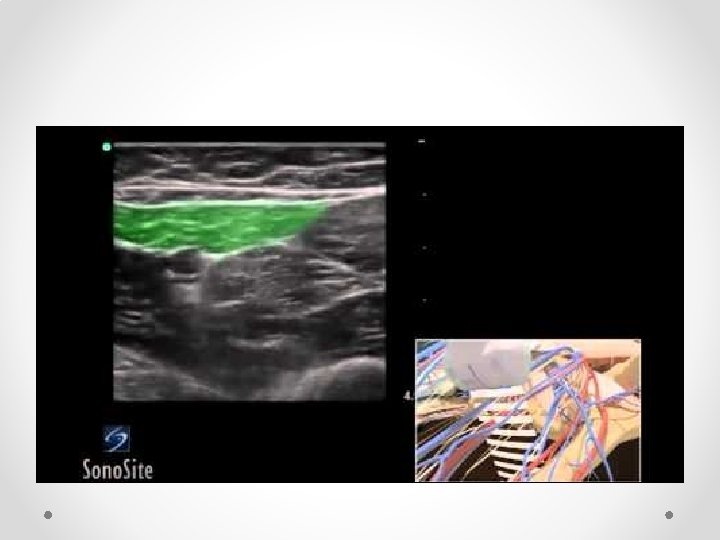

Rectus Sheath block for ACNES

Nerves run between IOM and Transversus abdominus, then posterior to rectus muscle before perforating through it to skin

Above (top) and below arcuate line NB below arcuate line (5 -10 cm below umbilicus) is no fascial sheath deep to rectus abdominus